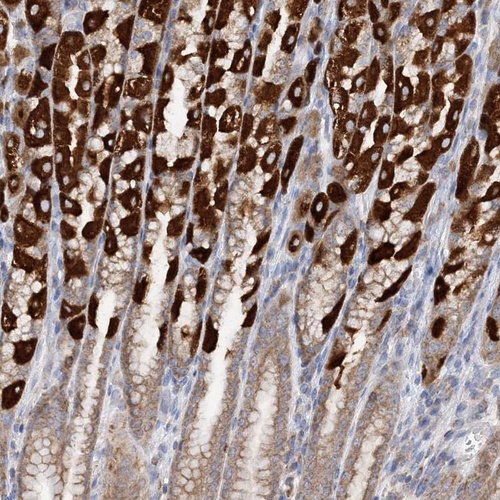

Immunohistochemical staining of human stomach shows strong cytoplasmic positivity in glandular cells.